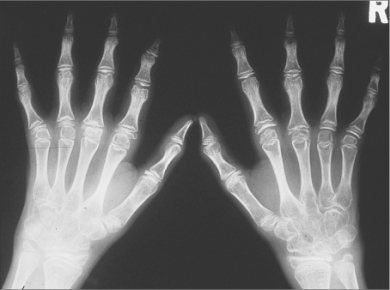

图2-7幼年型特发性关节炎(晚期)

11岁,双手数个掌指关节骨质侵蚀破坏,关节间隙狭窄,部分指间关节亦明显狭窄,右手第二指远侧指间关节半脱位(形成偏移畸形),腕骨融合

图2-8幼年型特发型关节炎(晚期)

12岁,双多个关节间隙狭窄,融合,其中多个关节偏移畸形。右腕骨明显骨质疏松,多个腕掌关节融合。右尺骨远端畸形,桡骨远端亦发育不好,系骨骺早闭所致